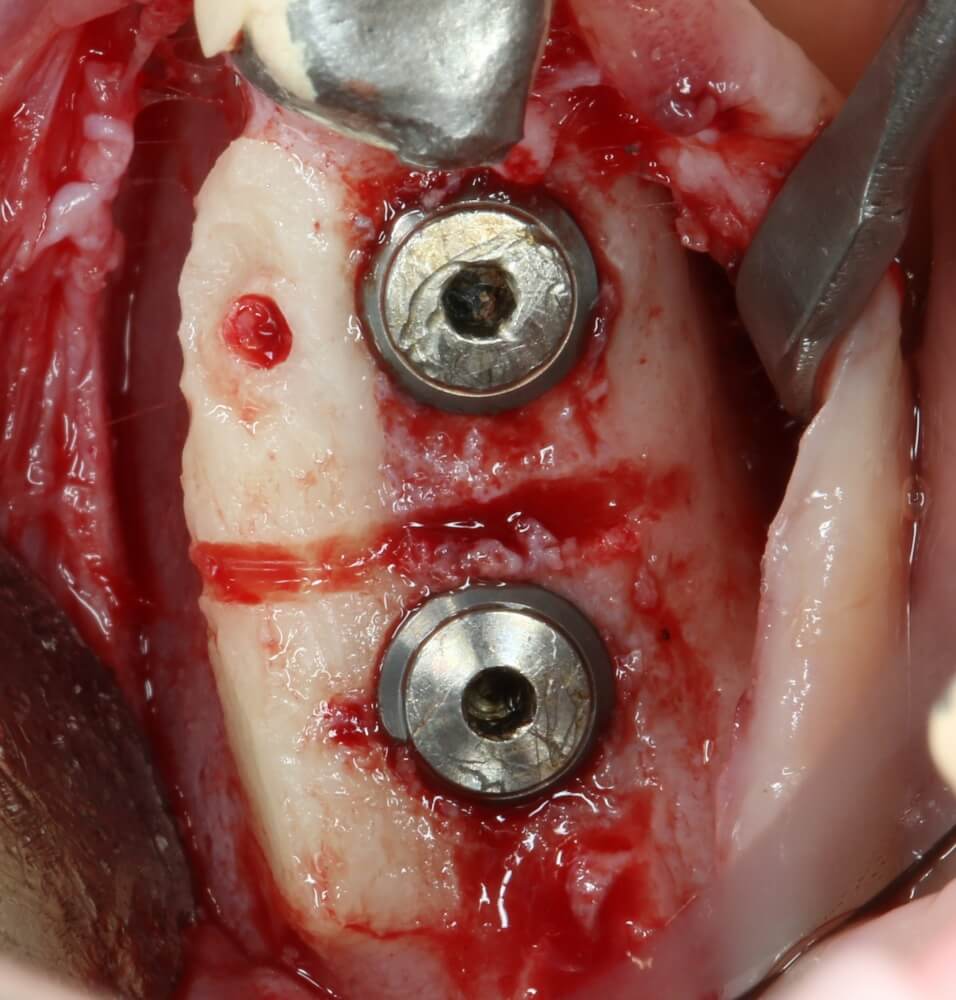

Подготовка костного ложа и фиксация аутотрансплантата

Возвращаемся к основной операционной области. Еще раз посмотрим на альвеолярный гребень, поофигеваем от его ширины и моих грандиозных планов:

Я зафиксировал костный блок практически без адаптации на несколько винтов. Обрати внимание, что винты находятся в зоне, где не планируется установка имплантатов. Фиксация должна быть надежной, поскольку мне еще предстояла подготовка лунок для имплантатов. Трех винтов для этого вполне достаточно.

Дальнейшая адаптация костного блока свелась к сглаживанию острых краев. После чего я приступил к подготовке лунок и установке имплантатов.

Установка имплантатов.

Напомню, что для этой работы я выбрал субкрестальные имплантаты Ankylos C/X. Они прекрасно сочетаются с любым методом остеопластики.

Глянем на то, что получилось:

Осталось адаптировать костный блок (убрать острые края), проверить его фиксацию и, при необходимости, добавить винты. Десятисекундное дело.